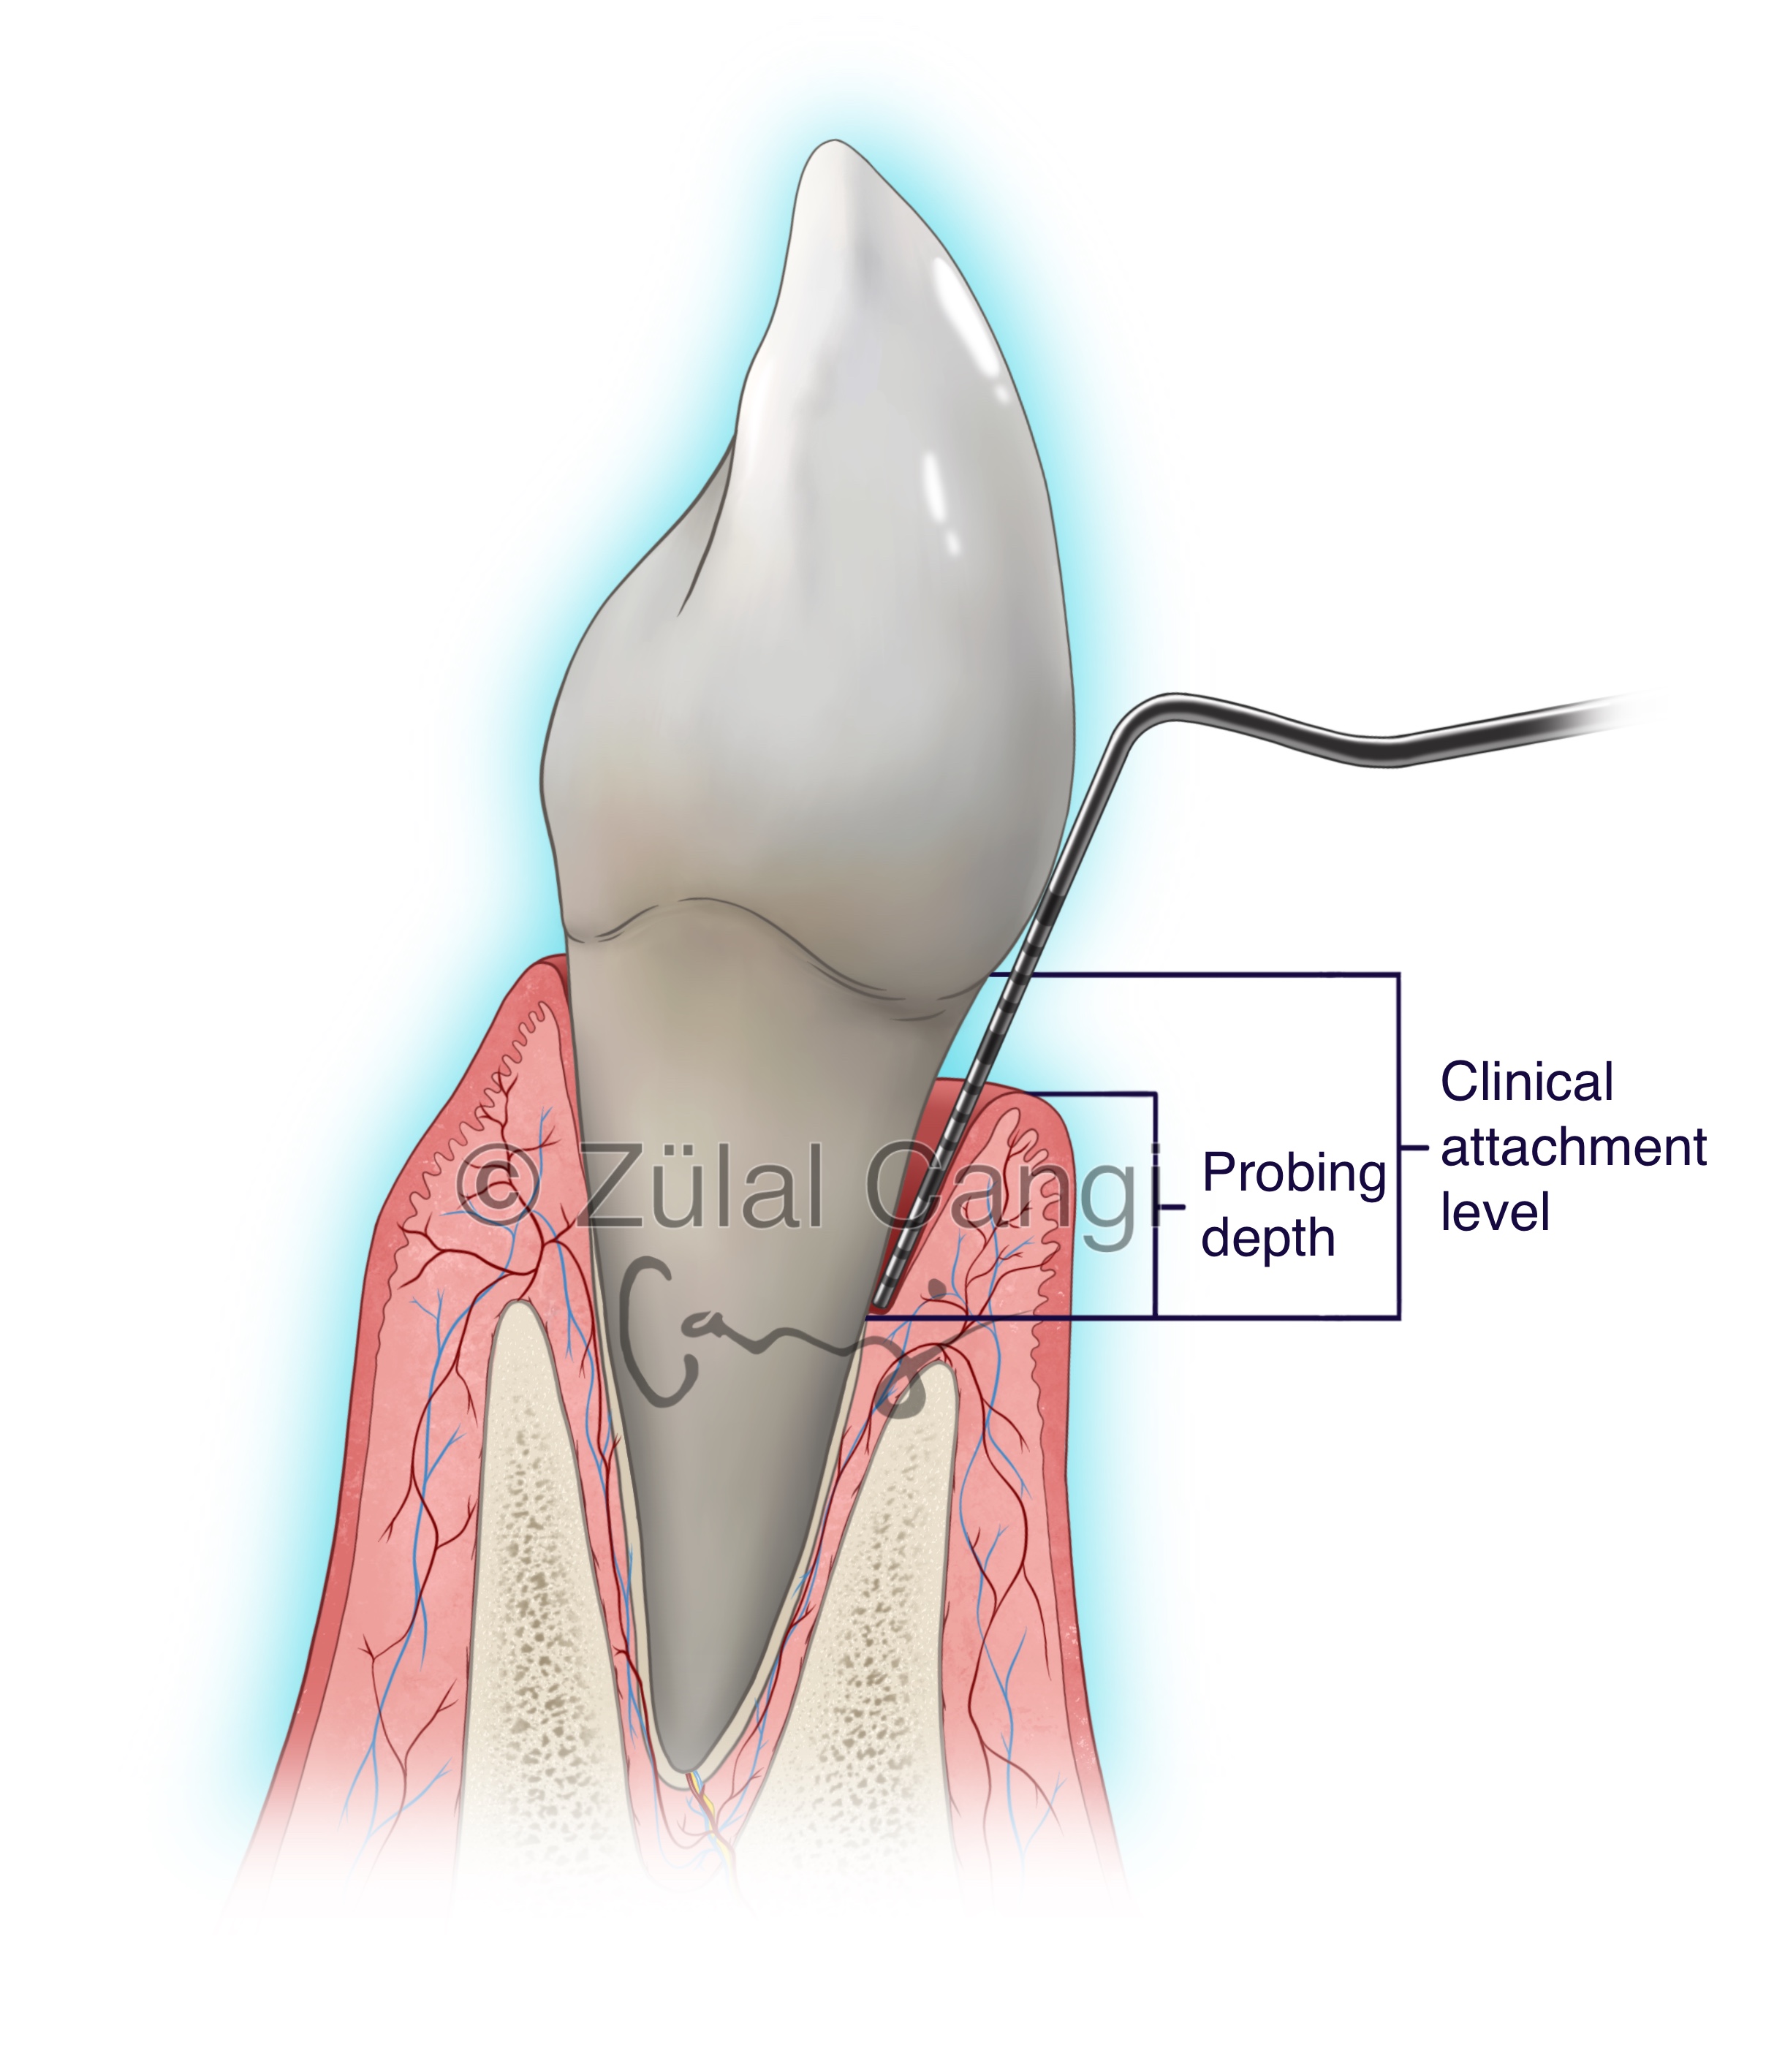

Sanatın estetiğini bilimin kesinliğiyle bir araya getiren Zülal Cangi, medikal ve bilimsel illüstrasyon alanındaki çalışmalarıyla akademik yayınlar, eğitim materyalleri ve çeşitli bilimsel platformlar için görsel içerikler üretmektedir. Amacı, bilimsel bilgiyi yalnızca doğru biçimde aktarmakla kalmayıp, aynı zamanda öğretici ve estetik bir dille görünür kılmaktır.

PORTFÖY